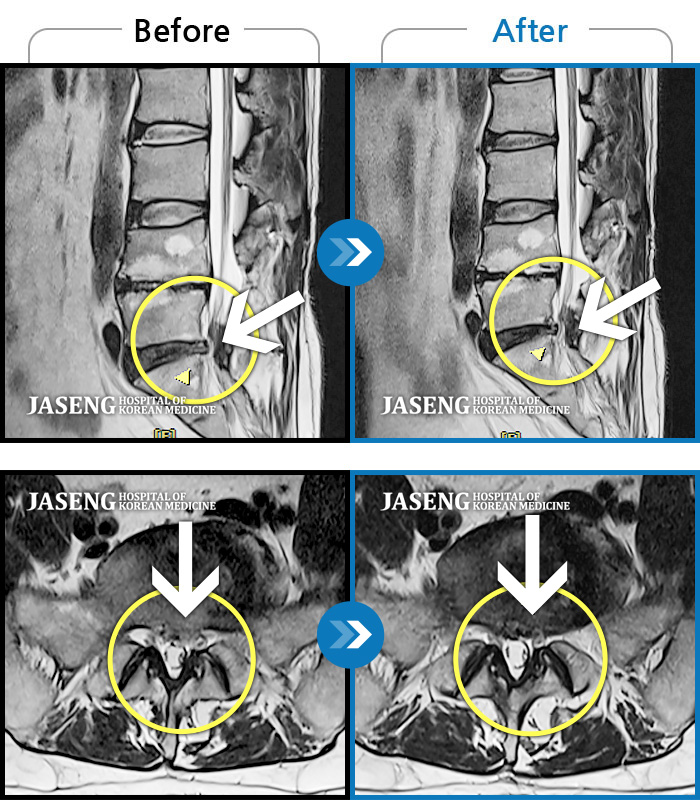

허리디스크

광주 · 장영우 원장

양측 허리부터 골반 묵직한 통증, 좌측 다리 외측까지 이어지는 당기는 통증으로 내원하셨습니다.

촬영시기

2503.04.01 ~ 2509.11.01

2025.09.22